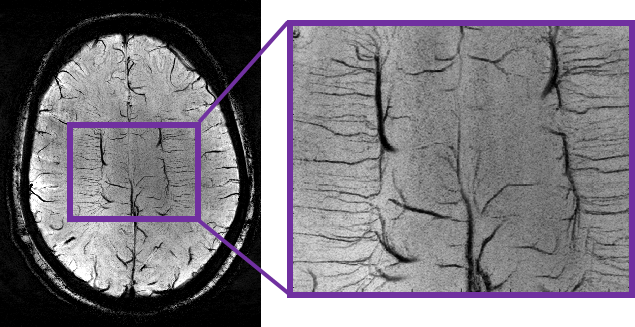

High resolution anatomical imaging